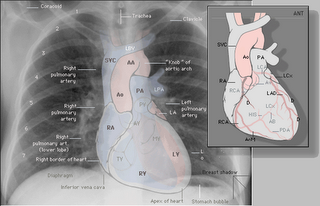

O coração não ouve e não fala. Quem vê, fala e ouve é sempre, e somente, o cérebro.

Esses equívocos são estimulados pela crença infantil que nossa razão e emoção estão em locais diferentes. Como eu já escrevi aqui, o coração era tido pelos antigos egípcios como a residência da alma, o responsável pelas emoções. Mas isso porque eles não tinham como dissecar uma pessoa para saber que na verdade o coração é apenas uma massa muscular que não faz outro a não ser bombear sangue, para o pulmão e para os outros órgãos e tecidos.

Meu coração partido não está no meu coração, está no meu cérebro.

Assim como todo o resto. Amor, lógica, raiva, álgebra, empatia, aritmética, filosofia, dúvida, decisão e geometria.